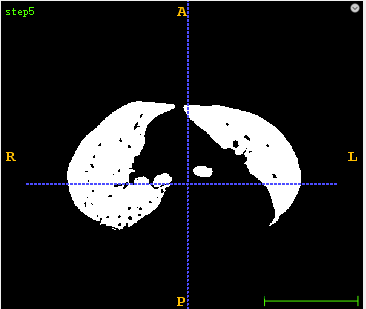

3、肺组织分割代码详解 3.1、 首先采用固定阈值区分肺组织和身体其它组织,设置固定阈值为-300。

3.2、 然后采用水漫金山法将肺组织和人体其它组织填充成一个区域。

3.3、 然后对固定阈值结果和水漫金山法结果先进行逻辑异或操作,然后再对其结果进行取反。

3.4、 对肺部内部区域进行填小洞操作。

3.5、采用连通域分析,去除小于最大物体一定比例的小目标物体。

3.6、采用区域生长得到气管分割结果。

3.7、 将第3.5步结果减去第3.6步结果。

3.8、 首先采用形态学开操作去除多余的边界区域,然后再采用形态学闭操作平滑肺组织轮廓,并填充肺部中中型空洞区域。

3.9、将得到的Mask图像与原始图像进行逻辑与操作得到最后的肺部分割结果图像。

def lungSegment(pathDicom): sitk_src = dicomseriesReader(pathDicom) # 1 sitk_seg = BinaryThreshold(sitk_src, lowervalue=-300, uppervalue=2000) sitk.WriteImage(sitk_seg, 'step1.mha') # 2 sitk_floodfilled = FloodFilled(sitk_seg) sitk.WriteImage(sitk_floodfilled, 'step2.mha') # 3 sitk_xorop = sitk.XorImageFilter() sitk_mask1 = sitk_xorop.Execute(sitk_seg, sitk_floodfilled) sitk_notop = sitk.NotImageFilter() sitk_mask2 = sitk_notop.Execute(sitk_mask1) sitk.WriteImage(sitk_mask2, 'step3.mha') # 4 sitk_mask3 = FillHole(sitk_mask2) sitk.WriteImage(sitk_mask3, 'step4.mha') # 5 sitk_mask4 = RemoveSmallConnectedCompont(sitk_mask3, 0.2) sitk.WriteImage(sitk_mask4, 'step5.mha') # 6 segtrachea lstSeeds = [] seed1 = [246, 268, 835] seed2 = [241, 287, 798] seed3 = [272, 277, 798] lstSeeds.append(seed1) lstSeeds.append(seed2) lstSeeds.append(seed3) sitk_tracheamask = RegionGrowThreshold(sitk_src, lstSeeds, -1024, -900) sitk.WriteImage(sitk_tracheamask, 'step6.mha') # 7 lung reduce trachea array_tracheamask = sitk.GetArrayFromImage(sitk_tracheamask) array_mask4 = sitk.GetArrayFromImage(sitk_mask4) array_mask4 = array_mask4 - array_tracheamask sitk_mask4 = sitk.GetImageFromArray(array_mask4) sitk_mask4.SetDirection(sitk_tracheamask.GetDirection()) sitk_mask4.SetSpacing(sitk_tracheamask.GetSpacing()) sitk_mask4.SetOrigin(sitk_tracheamask.GetOrigin()) sitk.WriteImage(sitk_mask4, 'step7.mha') # 8 sitk_mask4 = MorphologicalOperation(sitk_mask4, kernelsize=3, name='open') sitk_mask5 = MorphologicalOperation(sitk_mask4, kernelsize=9, name='close') sitk.WriteImage(sitk_mask5, 'step8.mha') # 9 sitk_lung = GetMaskImage(sitk_src, sitk_mask5, replacevalue=-1500) sitk.WriteImage(sitk_lung, 'step9.mha') return sitk_lung